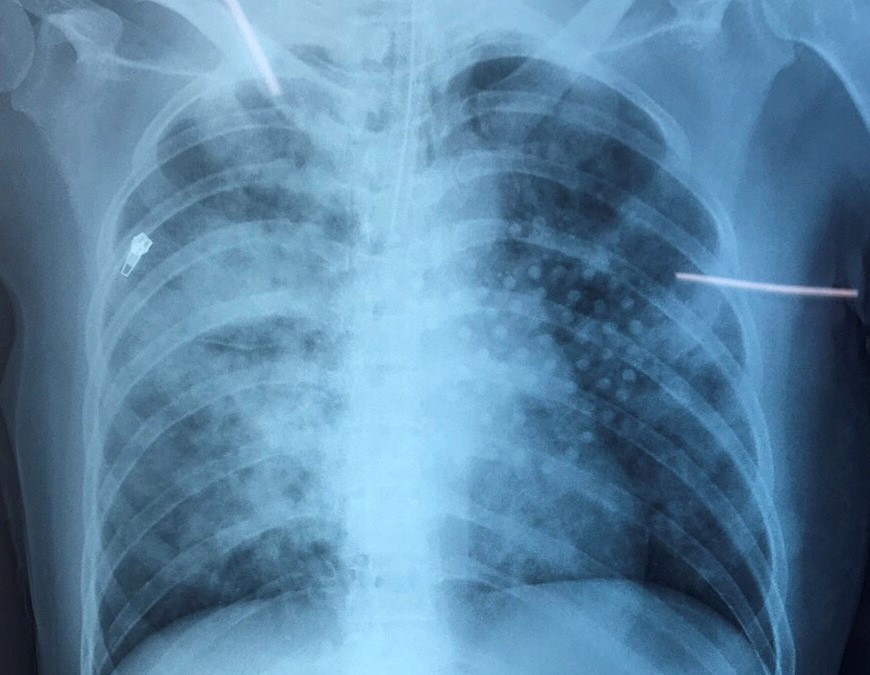

Tổn thương 2 bên phổi lan tỏa sau khi chị T. bị đuối nước. Thời điểm nhập viện, chị T. bị hôn mê, suy hô hấp nặng, huyết áp thấp. Tiếp nhận bệnh nhân, các bác sĩ đã tiến hành X-quang tim phổi thẳng. Kết quả cho thấy, chị T. bị mờ lan tỏa 2 phổi, gãy xương sườn.

Chẩn đoán, bệnh nhân bị viêm phổi hít, suy hô hấp cấp nguy kịch, hôn mê sau ngưng tim do ngạt nước. Trước tình trạng nguy kịch, chị T. được chuyển vào Khoa Hồi Sức Tích Cực – Chống Độc để điều trị.